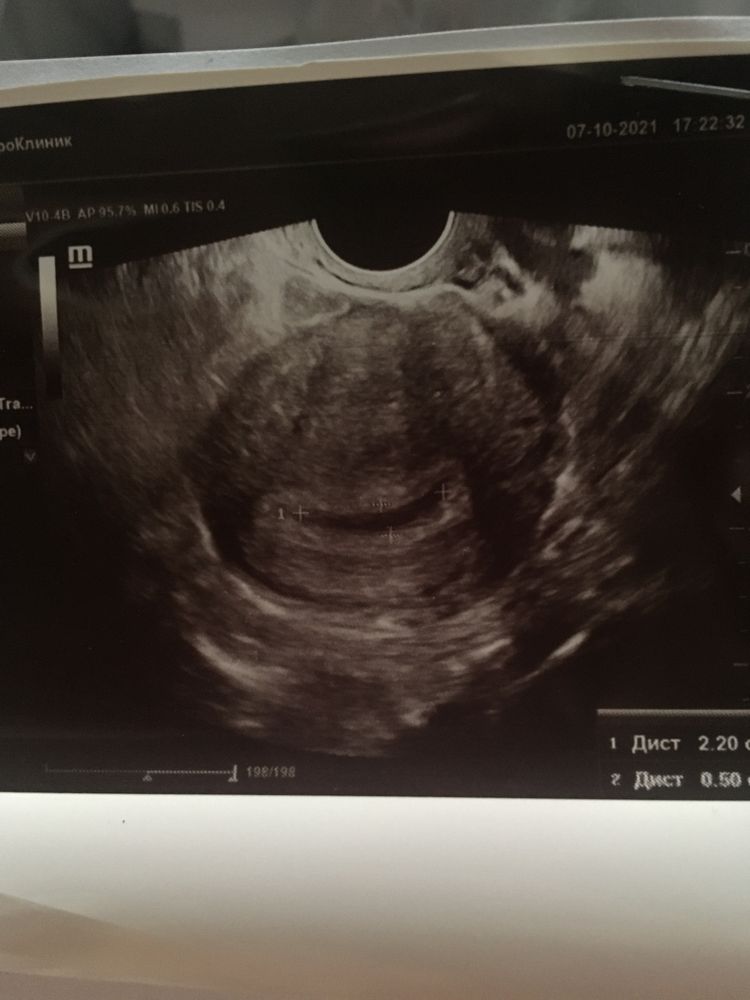

Тонус матки и образование в плодном яйце

Людмила, спасибо за ответ. Мы так долго ждали. Так обрадовались. Врач вчера испугал что это неблагоприятная беременность и мол она вам совсем не нужна.

Little Bunny, мне тоже говорили мол там не ребенок а ткань разрастается срочно аборт,а я сбежала от них и попала в другую больницу у меня была отслойка,месяц в больнице и выносила. Врачи не могут на таком сроке знать что там и права не имеют такое говорить суки. Не ходите туда больше. Идите в другую больницу

Людмила, я так и сделаю. И ХГЧ ещё завтра сдам. Каждый врач своё всегда говорит. Один мне выписал таблетки - другой говорит столько нельзя вам пить. А выкидыша ещё не было. Таблетки вчера не пила и сегодня ещё тоже.

Little Bunny, боли были крови нет. Но вообще это я всё к тому что у врачей бывает разные глаза руки воспитание и язык... Переделайте УЗИ в другом месте и потом уже принимайте решение.